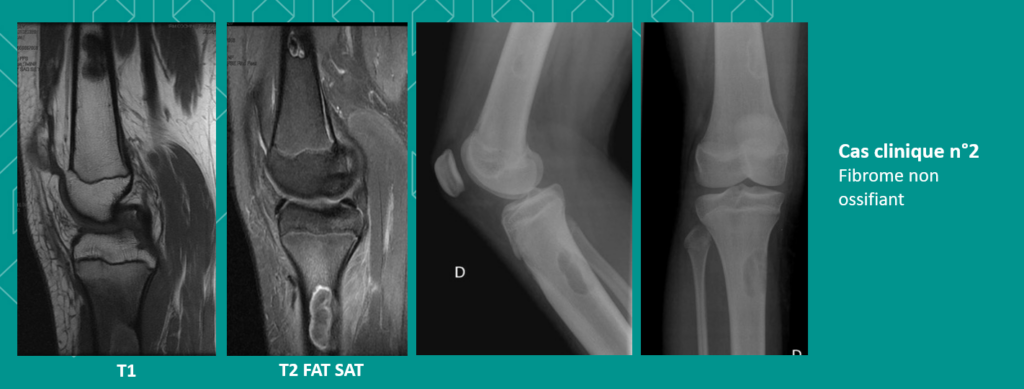

🔹N°2 – Jeune fille âgée de 13 ans : elle présente une gonalgie mécanique. A l’IRM, les images montrent deux lésions – une fémorale distale et une tibiale proximale, avec un œdème périlésionnel – ainsi qu’une rupture corticale avec une petite réaction des parties molles. La lésion est centrée sur la corticale avec une extension vers l’os spongieux et un liséré de sclérose autour. La radiographie réalisée ensuite permet de poser un diagnostic de fibrome non ossifiant, caractéristique par son liséré de sclérose périphérique. C’est une lésion fréquente (30 à 40% des enfants), souvent relevée lorsqu’on fait des radios de cheville et de genou, mais moins en IRM. La matrice est fibreuse, le signal T2 hétérogène, avec un rehaussement tardif et variable. La fracture est une des complications possibles. Pour ces lésions, une radiographie de complément permet de confirmer le diagnostic.